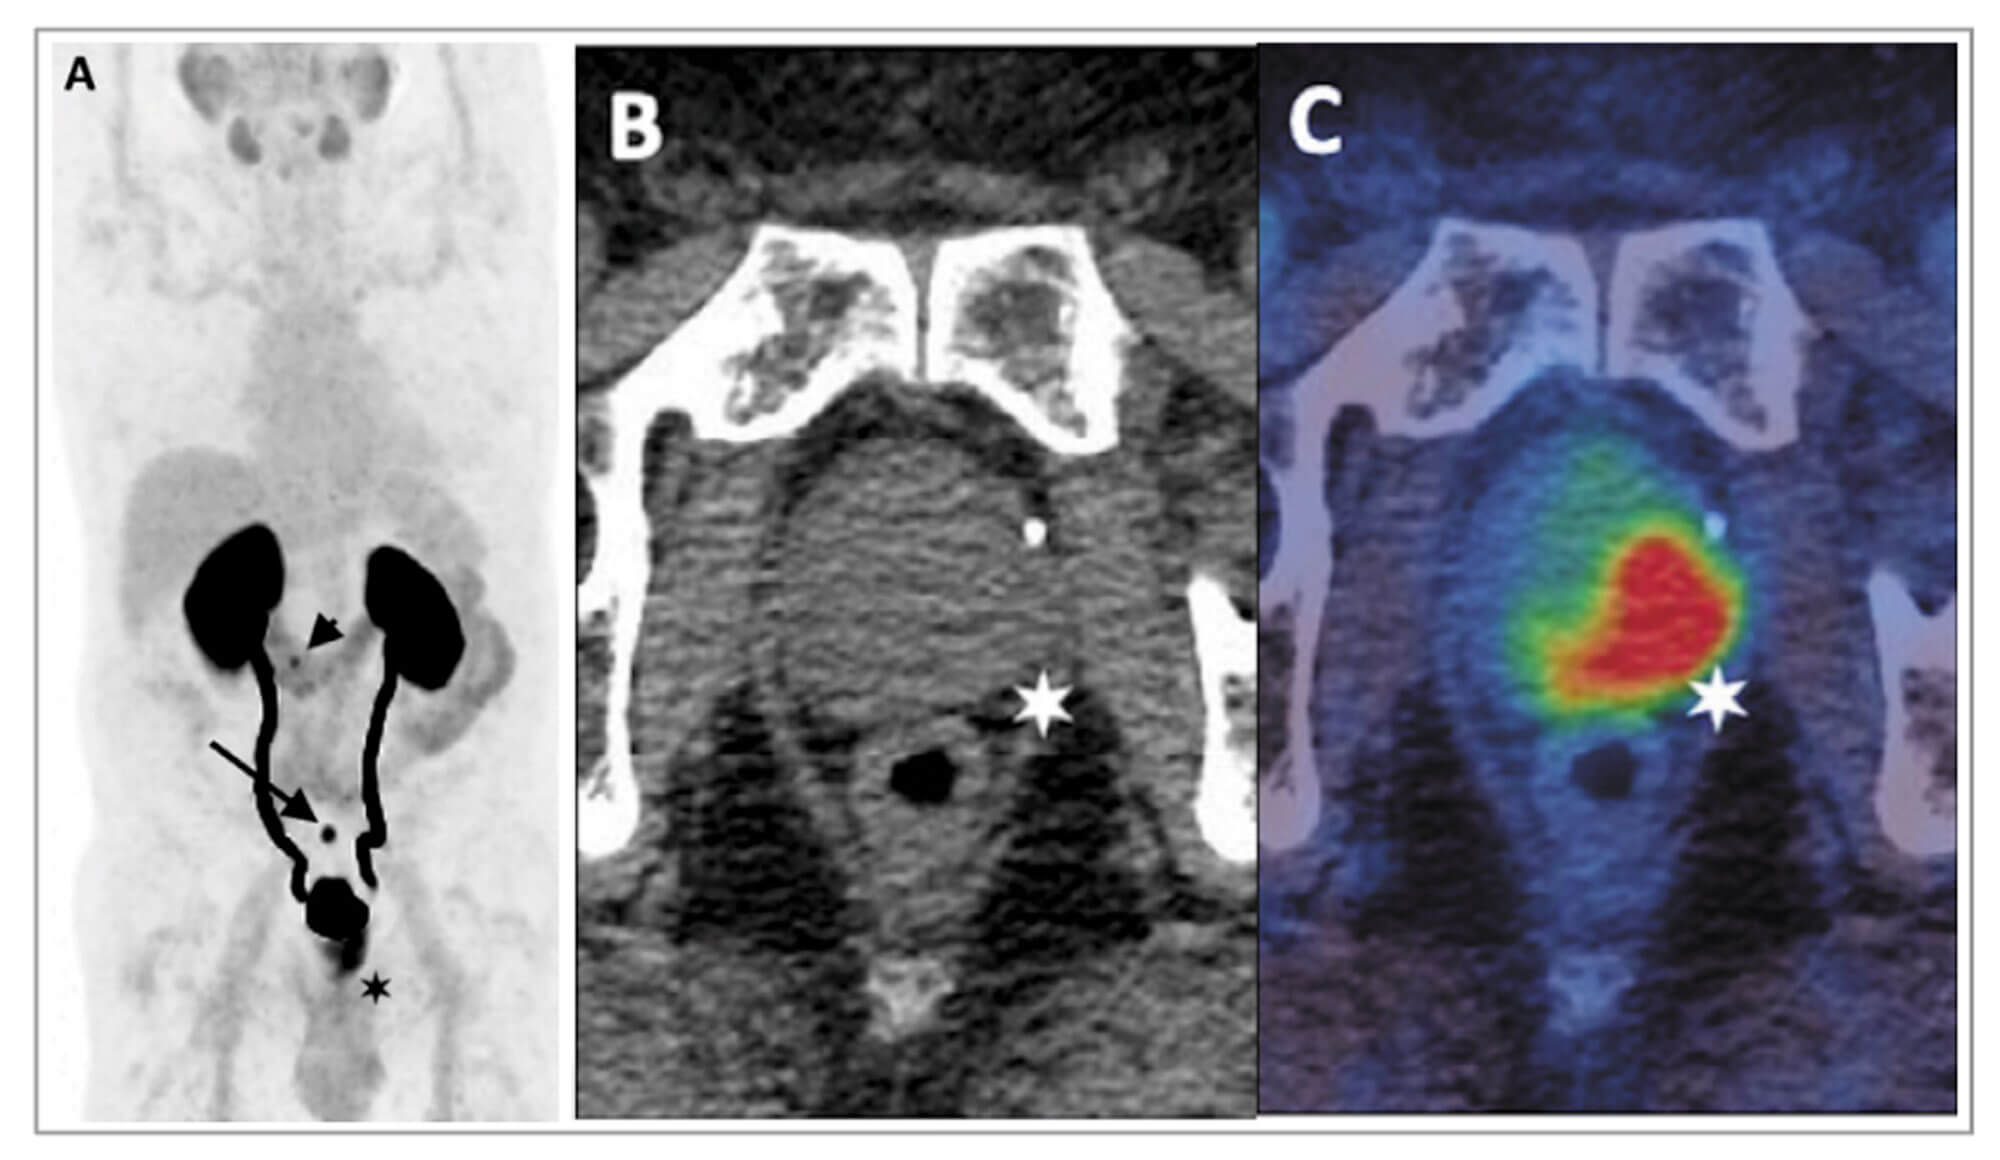

Figure 2: 68Ga-THP-PSMA PET-CT in staging of primary prostate cancer.

A: PET image B: Axial CT C: Fused PET-CT image

Images demonstrate high-grade uptake in a predominantly left-sided prostatic tumour

with low-grade uptake in a 6mm left internal iliac node (arrow on PET, star on fused images).

There are an increasing number of studies demonstrating the superiority of 68Ga- labelled PSMA PET-CT over conventional imaging for CaP staging (Figure 2). A prospective study of 113 patients confirmed significantly higher sensitivity (96.2% vs. 73.1%) and accuracy (99.1 vs. 84.1%) using 68Ga-labelled PSMA PET-CT compared with BS for metastatic bone disease [8].

Several studies have assessed the diagnostic performance of 68Ga-labelled PSMA PET-CT for nodal staging with histopathological validation. The largest series of 208 patients reported a sensitivity for nodal disease of 38.2% (21 of 55 patients) and a per node sensitivity of 24.4% (42 of 172 nodes). The median diameter of a malignant node was 4.8mm, with 15% of histologically-proven malignant nodes measuring <5mm [9].

The ProPSMA study, an Australian, multicentre, prospective, randomised controlled trial, of 300 patients with a primary CaP, compared 68Ga-labelled PSMA PET-CT with conventional imaging [10]. PSMA PET-CT had a 27% greater accuracy compared to conventional imaging (92% vs. 65%). The results of conventional imaging resulted in a treatment change for 23 men compared with 41 men following PSMA PET-CT. Conventional imaging was also associated with a higher radiation dose (19.2mSv compared to 8.4mSv). The group have also reported data on favourable cost outcomes of PSMA PET-CT, further demonstrating the clinical utility of this technique [10].